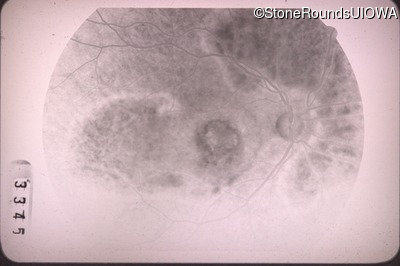

Fluorescein Angiography - Left - 20/40 -1

Exemplar